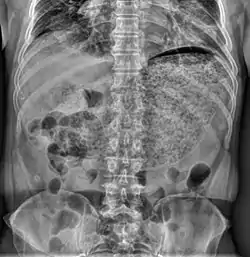

Gastroparese

Gastroparese er en medicinsk tilstand med parese (delvis lammelse) af maven, der resulterer i at føde bliver i mavesækken i længere tid end normalt. Almindeligvis sørger peristaltiske bevægelser i maven for at føden bevæges videre ned i tyndtarmen for videre fordøjelse; denne proces styres af nerven nervus vagus. Gastroparese kan opstå når nervus vagus er beskadiget og musklerne omkring maven og tarmene ikke fungerer normalt. Resultatet er at føden bevæger sig langsomt gennem mave-tarmkanalen, eller slet ikke bevæges videre gennem systemet.